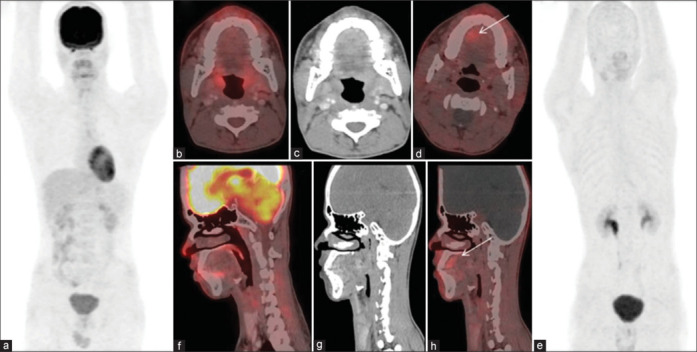

Mucosal melanomas (MMs) represent a rare subset of melanomas arising from melanocytes in noncutaneous sites such as mucosal membranes of the head-and-neck, gastrointestinal, and genitourinary tracts. Unlike cutaneous melanomas, MMs often present late due to their occult nature, leading to a poor prognosis. Fluorine-18 fludeoxyglucose positron emission tomography/computed tomography (18F-FDG PET/CT) is widely utilized for staging and monitoring melanomas, leveraging their characteristic high FDG avidity. Recently, fibroblast activation protein inhibitor (FAPI)-based PET/CT imaging has become a popular modality in the evaluation of various cancers. Here, we present a case of MM where FDG avidity was notably absent and mild FAPI avidity, despite the lesion's typical anatomical location and clinical suspicion. This case highlights an uncommon scenario within the literature and underscores the variability in radiotracer uptake observed in MMs, challenging conventional imaging expectations and potentially impacting clinical management decisions.

Abstract Image